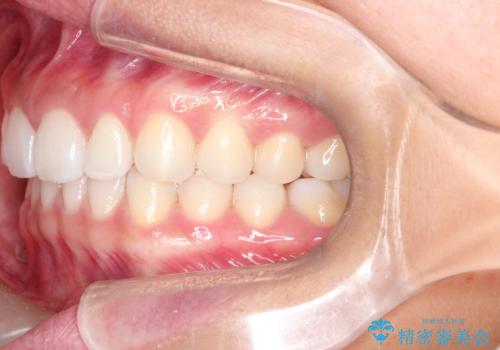

すきっ歯のインビザラインによる目立たない矯正

- すきっ歯を治したいとのことで来院されました。

上下ともに前歯に隙間がありました。

目立たない装置をご希望のためインビザラインで矯正治療を行うこととしました。

使用時間を守っていただけたので、スムーズに治療を終わることができました。